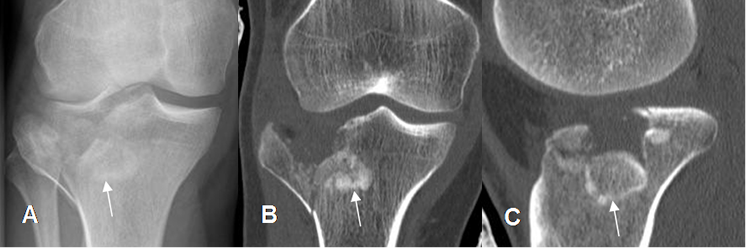

Fig 43. Fractura de la tibia.

A: Rx digital AP, B: TAC axial y C: TAC reconstrucción coronal. Fractura lineal y no deprimida, del platillo tibial lateral.